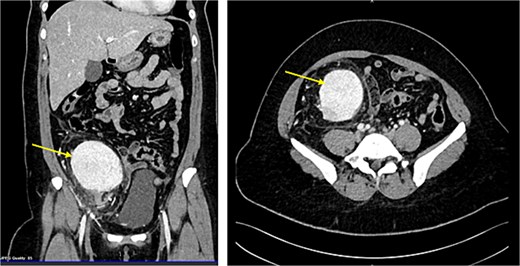

CT scan revealed evidence of large right iliac fossa soft tissue mass, measuring 8.5 × 8.2 × 8.4 cm, displacing the adjacent abdominal and pelvic organs with significant peri-lesional fat strandings. The mass shows homogenous hyper enhancement in post contrast with peripheral slight enhancing area [3.3 × 1.8 cm] with adjacent bowel loops tethering with peritoneal thickening. There were multiple adjacent para-aortic, right external iliac, and common iliac lymph nodes enlargement (Fig. 1). The mass vessels were arising from the right external iliac artery and vein (Fig. 2).

(A) CT abdomen with contrast demonstrating the mass in the right iliac fossa. (B) The image is rotated to show the blood supply from right external iliac artery and vein.